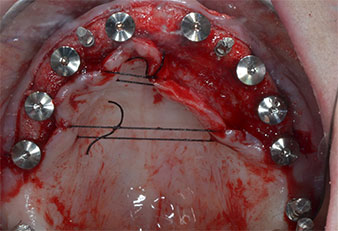

Wegen des relativ harten Knochens (D2) an den Positionen 11 und 21 wurden die 10 mm langen Implantatlager in diesem Bereich abschließend mit einem 4-mm-Spiralbohrer, dem chirurgischen Winkelstück WS-75 L von W&H und dem W&H Implantmed Implantologiemotor in Verbindung mit dem optionalen W&H Osstell ISQ module präpariert. Im Gegensatz dazu wurde der weiche Knochen der Implantatlager im Seitenzahnbereich mit dem Piezomed I3P auf den abschließenden Durchmesser von 3 mm erweitert. Die Implantate wurden dann transgingival eingesetzt, die Einheildauer betrug drei Monate (Abb. 6-10). Die vorhandene Prothese wurde auf vier provisorischen Implantaten abgestützt (Abb. 8).

10-mm-Tissue-Level-Implantat

Abb. 6: Ein 10-mm-Tissue-Level-Implantat wird an Position 21 platziert. Das Implantat an Position 11 und die drei linken posterioren 4-mm-Implantate wurden bereits eingesetzt.

Implantatstabilität

Abb. 7: Die Implantatstabilität wird mit einem SmartPeg und dem W&H Osstell ISQ module ermittelt. Alle Werte befinden sich im mittleren bis hohen Bereich, mit einem Mindestwert von 69.

provisorische Implantate

Abb. 8: Nach Befestigung der Gingivaformer werden an den Positionen 18, 12, 22 und 28 provisorische Implantate eingesetzt.